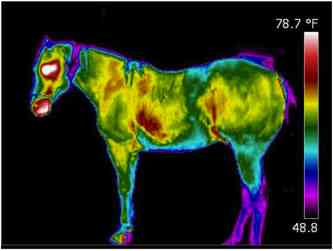

TheraPlate Imaging

One of the primary therapeutic mechanisms of the TheraPlate is increasing circulation, both immediately and long-term. The short-term impact can be seen via thermograms. Here we see "Buck" imaged before and during a session on the TheraPlate. Notice the significant increase in skin temperature across much of his body, particularly those areas with large muscle mass. This can be attributed to the increased blood flow to those areas as the muscles react to the motion of the TheraPlate.